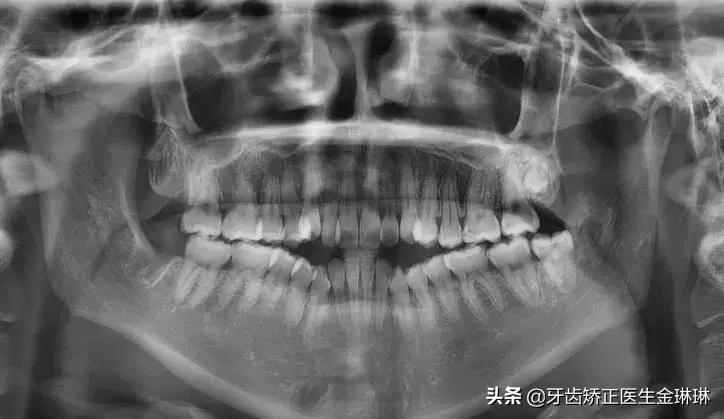

本文详细解析开颌的成因、危害及矫正方案,涵盖儿童、青少年、成人不同年龄段的治疗时机与方法,包括功能性矫治器、固定矫治器、外科手术...